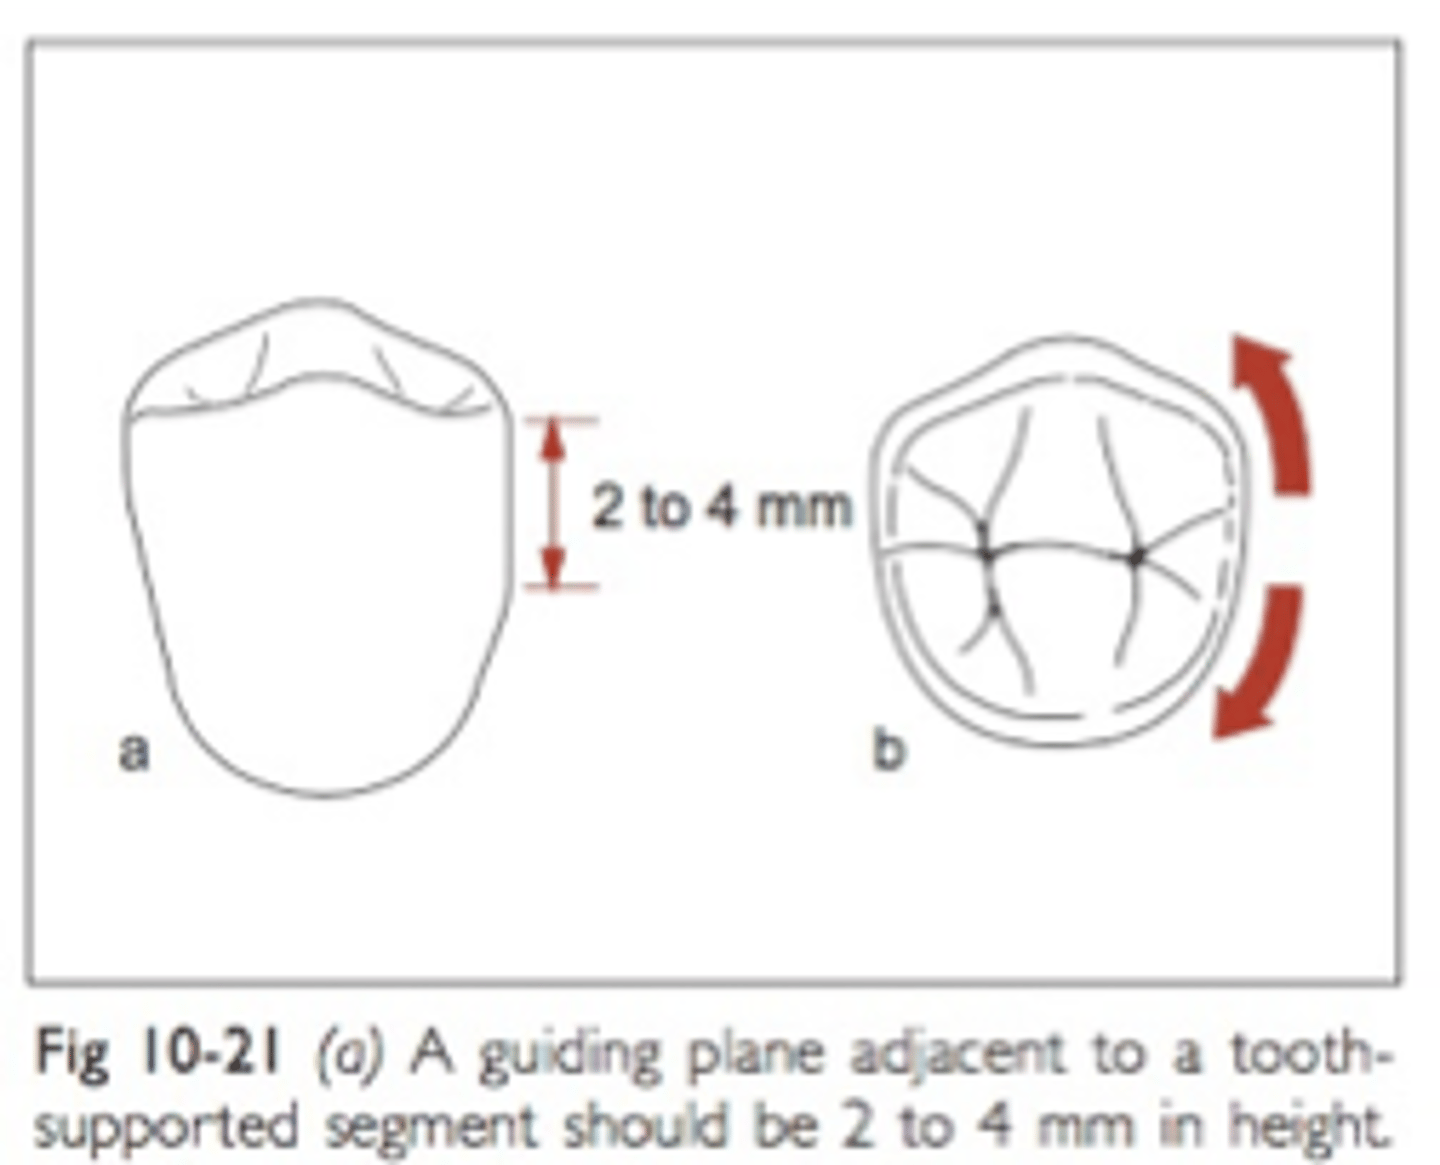

Guide planes

Are prepared (occasionally natural) axial surfaces of teeth against which the RPD glides during insertion and removal - defines the path of insertion

parallel

Guide planes must be ______ to each other and to the path of insertion

occlusal

Guide planes are Located in the _____ portion of the tooth (a proximal or lingual plate refers to the part of the RPD framework that is in contact with the guide plane)

natural curvature of the tooth buccolingually

Whether adjacent to tooth-borne or extension base segments, the prepared surface for RPD should not be a straight “slice” buccolingually, but should follow the ....